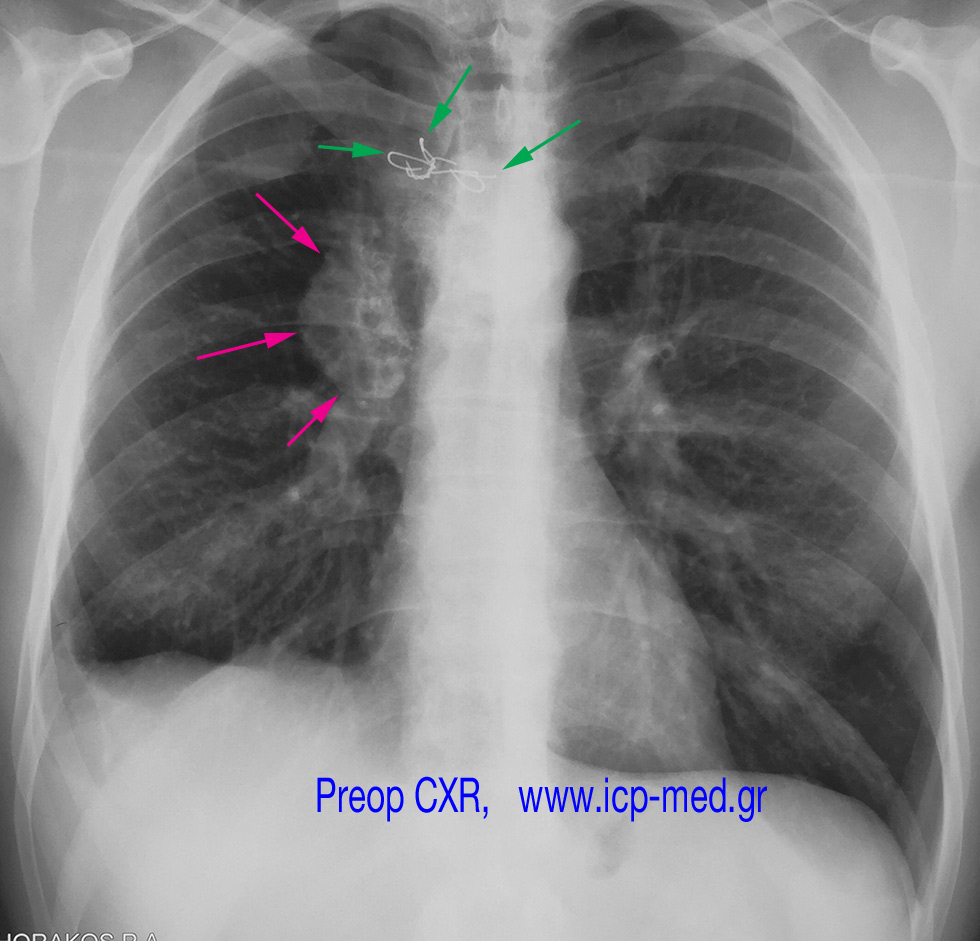

2. PreOp CXR. Magenta arrows: the tumour. Green arrows: steel wire elsewhere 14 yrs before